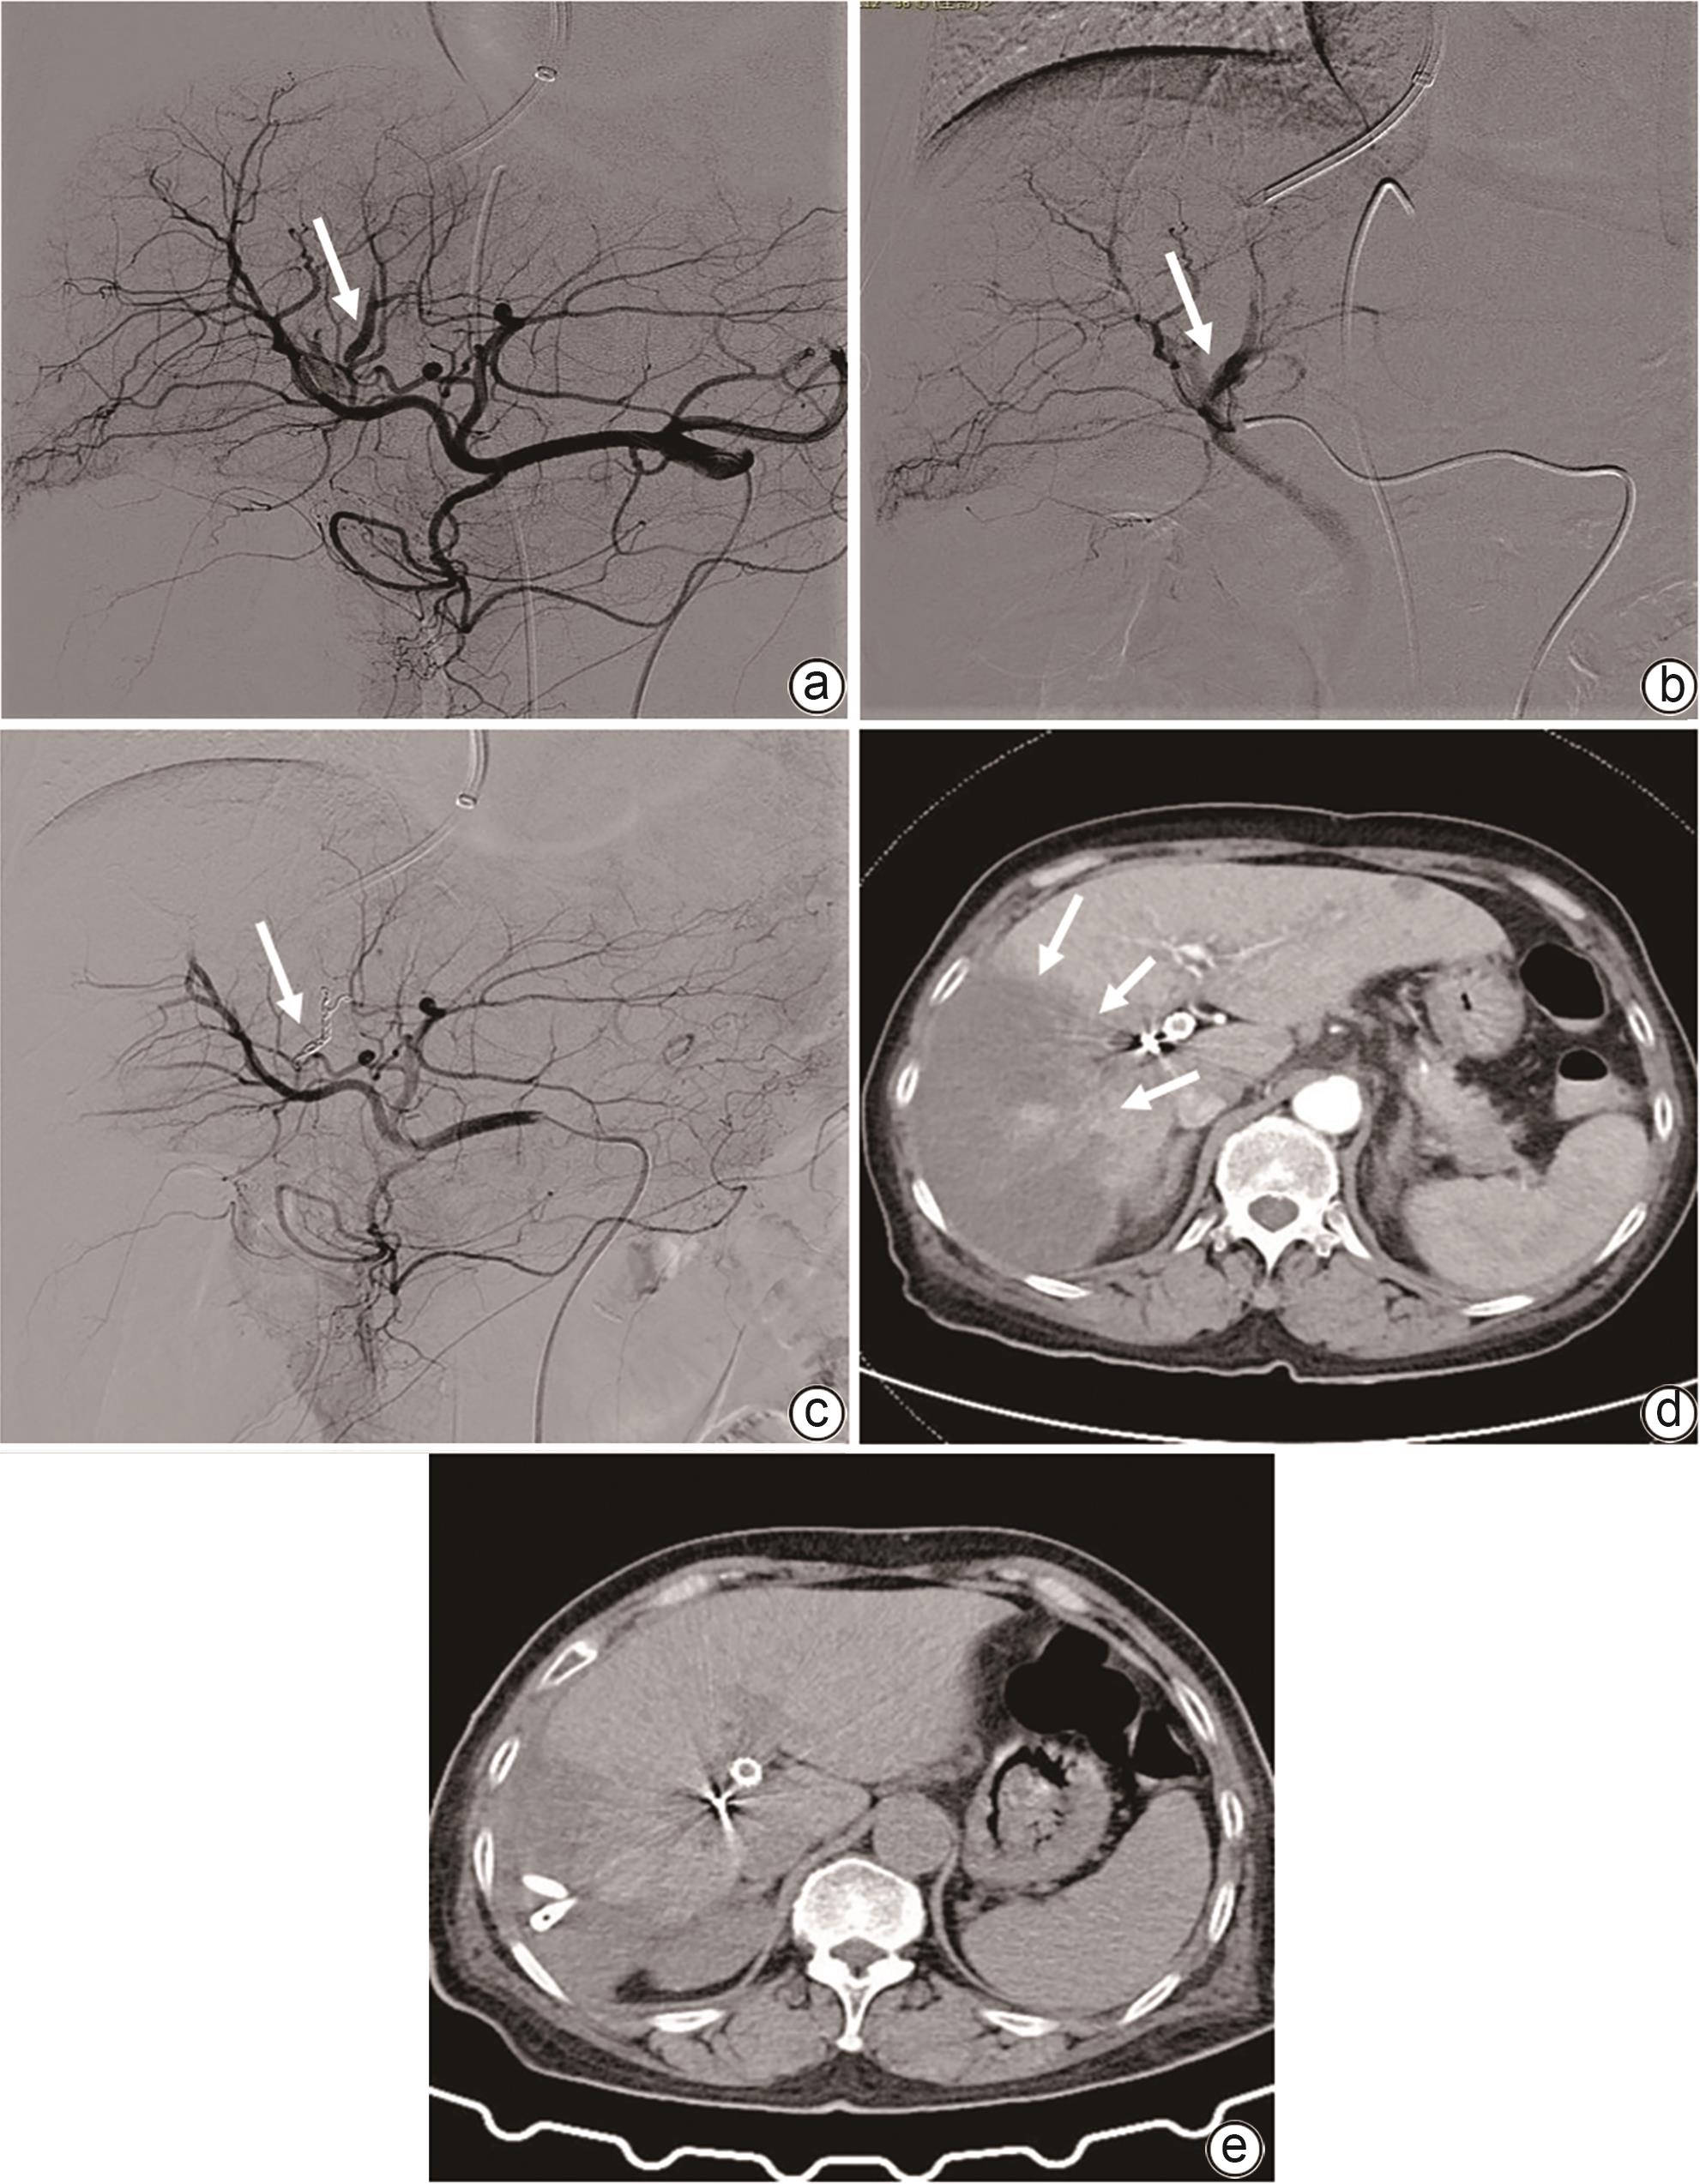

Imaging features and therapeutic strategies for lethal iatrogenic hemobilia

Chen WANG, Min WANG, Ke ZHANG, Jinxing ZHANG, Li LIU, Zhining FAN

2024, 40(10): 2070-2074. DOI: 10.12449/JCH241022

Abstract(1032) HTML (357) PDF (2026KB)(84)

Abstract:

Objective  To investigate the imaging features and pathogenesis of lethal iatrogenic hemobilia (LIH) and the value of transarterial intervention in the treatment of LIH.  Methods  A total of 269 patients with upper gastrointestinal bleeding who were admitted to The First Affiliated Hospital of Nanjing Medical University from August 2009 to July 2023 were enrolled, among whom 24 had a confirmed diagnosis of LIH and received treatment, and a retrospective analysis was performed for the clinical data of these 24 patients, including the iatrogenic causes, angiographic findings, and arterial interventions of LIH. Among the 24 patients, 23 received transarterial embolization (TAE) with gelatin sponge particles and coils, and 1 received a covered stent for isolation. The main criteria for assessing treatment outcome included the technical success rate of surgery, procedure-related complications, and long-term clinical follow-up.  Results  Among the 24 patients with LIH, 12 had LIH caused by interventional procedures, and 12 had LIH caused by hepatobiliary and pancreatic surgery. The main clinical manifestations included a significant reduction in blood pressure or a persistent reduction in hemoglobin in 13 patients and upper gastrointestinal bleeding in 18 patients. Among the 24 patients, 2 developed symptoms during surgery, 4 developed symptoms within 24 hours, and 18 developed symptoms after 24 hours. Angiography showed a positive bleeding rate of 100% (24/24), and imaging findings included pseudoaneurysms in 15 patients, hepatic artery truncation in 3 patients, extravasation of contrast medium in 5 patients, and hepatic arteriobiliary fistula in 3 patients. Among the 24 patients, 23 received TAE and 1 received stent implantation. Successful hemostasis was achieved for 23 patients, with a technical success rate of 95.8% (23/24). Four patients developed hepatic necrosis and abscess after TAE, and there was no rebleeding or recurrence after hemostatic treatment.  Conclusion  Various iatrogenic injuries may result in LIH with diverse clinical and imaging findings, and integrated diagnostic imaging combined with transarterial intervention is the best effective life-saving measure for LIH.